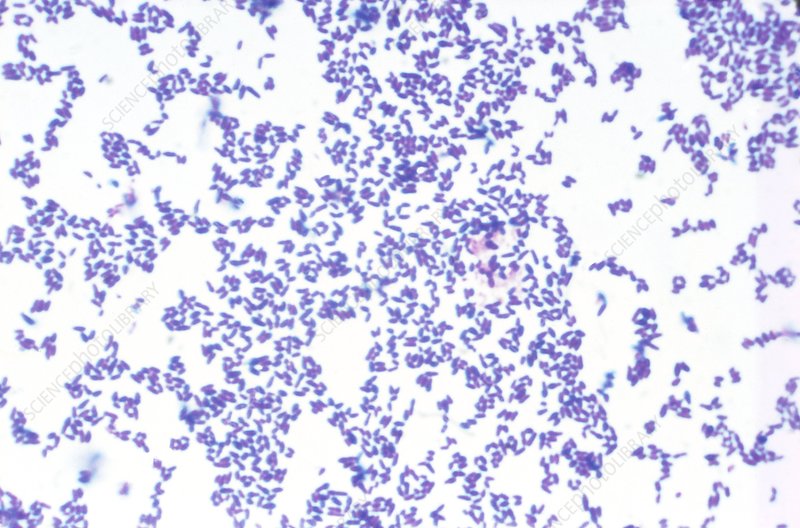

코리네박테리움 디프테리아( Corynebacterium diphtheriae )라는 박테리아 유형이 디프테리아를 유발합니다. 이 상태는 일반적으로 사람 대 사람 접촉을 통해 또는 컵이나 사용한 티슈와 같이 박테리아가 있는 물체와의 접촉을 통해 퍼집니다. 감염된 사람이 재채기, 기침 또는 코를 풀 때 주변에 있으면 디프테리아에 걸릴 수도 있습니다.

감염된 사람이 디프테리아의 징후나 증상을 나타내지 않더라도 초기 감염 후 최대 6주 동안 세균 감염을 전염시킬 수 있습니다. 박테리아는 가장 일반적으로 코와 목을 감염시킵니다. 일단 감염되면 박테리아는 독소라는 위험한 물질을 방출합니다. 독소는 혈류를 통해 퍼지고 종종 신체의 코, 목, 혀, 기도 등과 같은 부위에 두꺼운 회색 코팅이 형성됩니다.